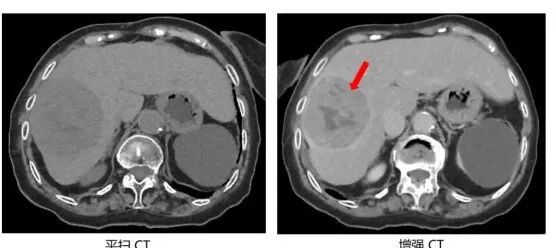

下面我们来看看平扫CT和增强CT的差别。下图分别为肝脏和肾脏平扫CT图像与增强CT图像的比较,在增强CT上医生可更清晰的发现肝脏和肾脏的病变,且对病变的良恶性判断有帮助。